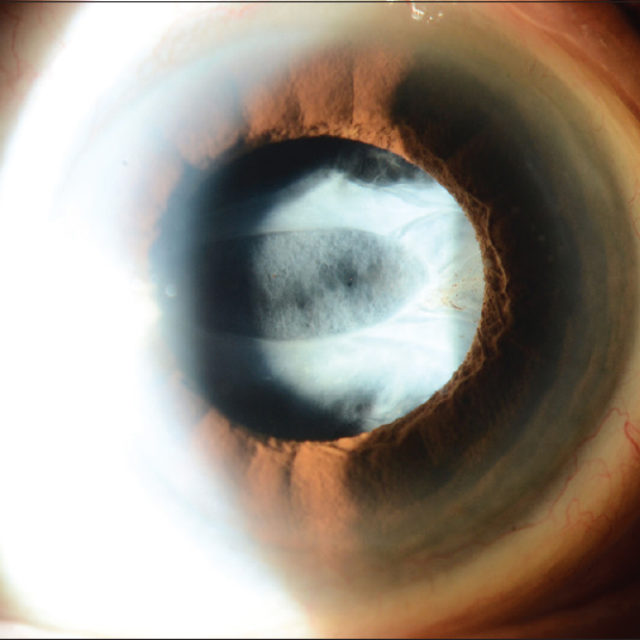

Пігментний ретиніт уражає мільйони людей у світі та є однією з провідних причин спадкової втрати зору. Незважаючи на те, що хвороба прогресує повільно, а деякі пацієнти зберігають зір до середнього віку, механізми адаптації сітківки до втрати клітин залишаються погано вивченими. Вивчення таких механізмів може відкрити нові терапевтичні цілі для збереження зору.